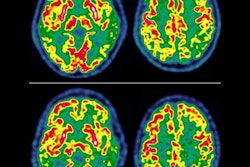

A discordant case of a patient with Alzheimer's disease (AD), correctly classified with FDG-PET based on hypometabolism in the left posterior cingulate gyrus (red arrow) extending to the precuneus, but wrongly diagnosed based on MRI-eASL perfusion. Images courtesy of Ceccarini et al.